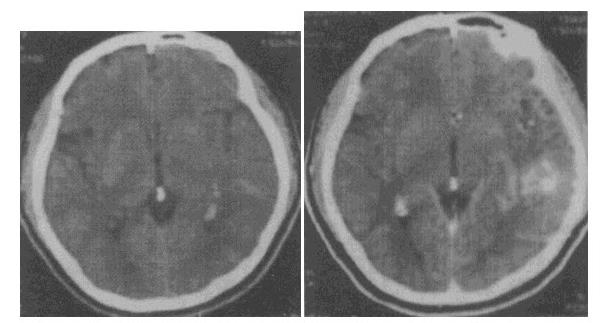

- 单项选择题 男性,39岁,“癫痫”发作2次,无发热、肢体活动不适等症状,根据其CT平扫及强化图像(见图),应首先考虑以下何种诊断()。

- B